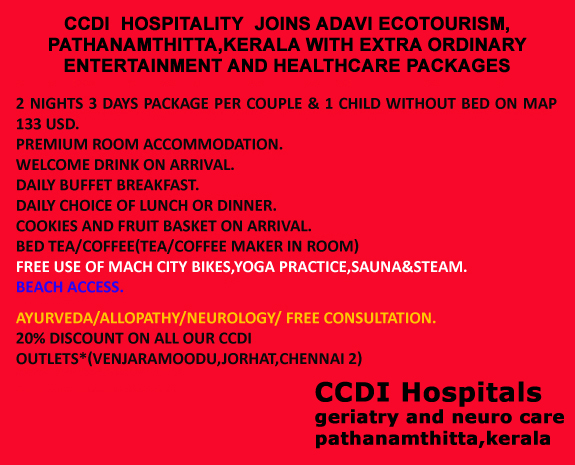

One additional room for 2 children upto 12 years of age on room only basis-valid

only between 1st October and 30th December(subject to availability)*